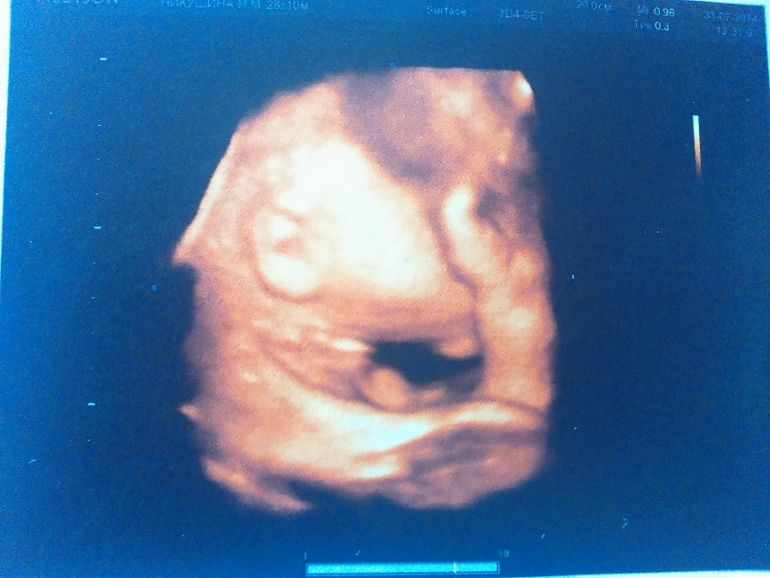

Лежит наш слоненок головой вниз, прижавшись к стенке матки носом, поэтому 3Д фотографии личика не очень вышли хорошо. зато причиндалы демонстрировал охотно)))

ну и пара фоточек (не очень лицо видно было, но разглядели папины щеки и губы и мой нос))))

ушко)